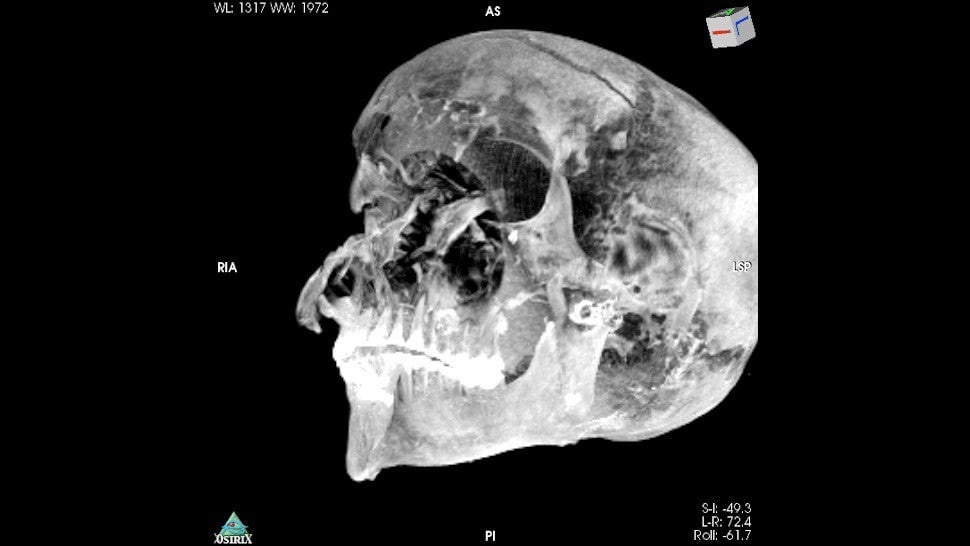

Hace más de un siglo, se encontró la momia de un adolescente en Nag el-Hassay, Egipto. Su cuerpo permanece envuelto, pero un equipo de investigadores ha usado tomografía computarizada para mirar a través de las sábanas y lo que ha descubierto son 49 amuletos dentro del cuerpo.

La momia estaba en un cementerio ptolemaico a unas 500 millas al sur de El Cairo, lo que significa que los restos tendrán unos 2.300 años. Las tomografías computarizadas que realizó el equipo también revelaron detalles de la salud del niño antes de morir. Su investigación se publica hoy en Frontiers in Medicine.

Al igual que el faraón Tutankamón, la momia estudiada recientemente era un hombre de alto nivel socioeconómico que murió joven, a alrededor de 14 o 15 años de edad, según la medición de los investigadores. Medía alrededor de 128cm de alto.

En un correo electrónico remitido a Gizmodo, Saleem explicó que el equipo no pudo determinar la causa de la muerte. Por lo que pudieron ver, el niño gozaba de buena salud. Dado que los órganos internos fueron removidos durante el proceso de momificación, los signos de enfermedad que pudieron haber estado en las vísceras han desaparecido hace mucho tiempo. Además de los artefactos de oro en su cuerpo, la momia está adornada con hojas de helecho. La parte posterior de la cabeza del niño está llena de una resina ahora solidificada.